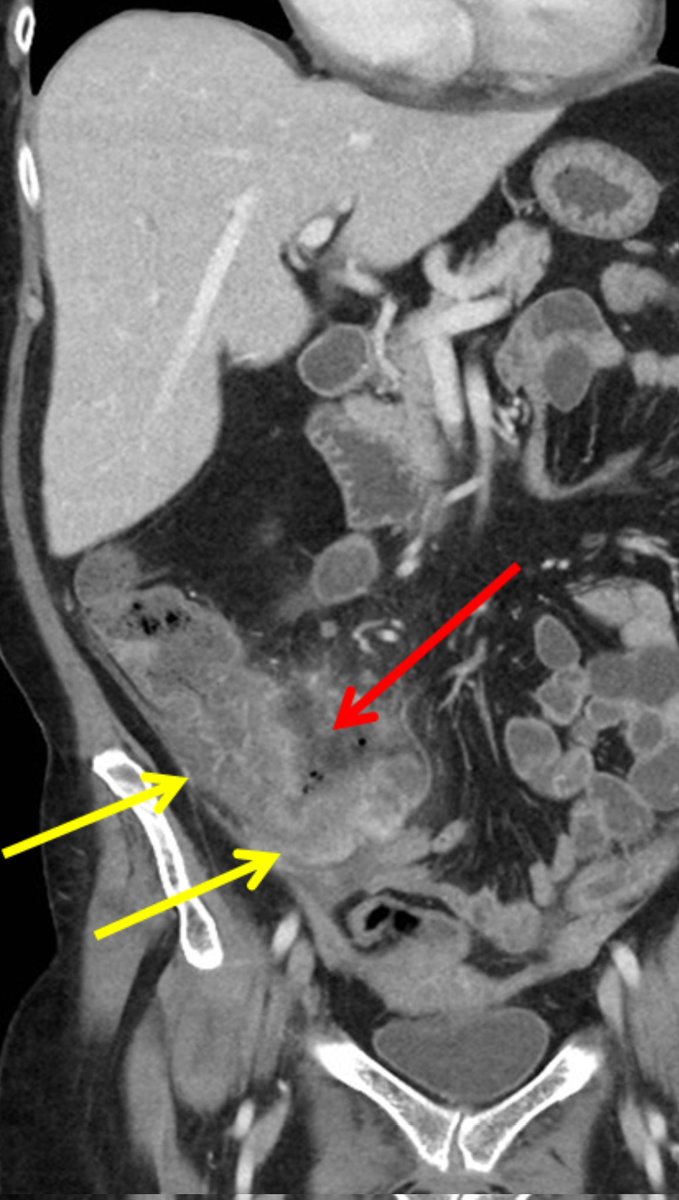

Diarrhoea 😭😭

≥ 3 unformed stools/day, can be much more in these patients!

Causes:

-Chemotherapy/Radiation

-Neutropenic colitis

-Antibiotics

-GVHD

-INFECTIONS, INFECTIONS, INFECTIONS